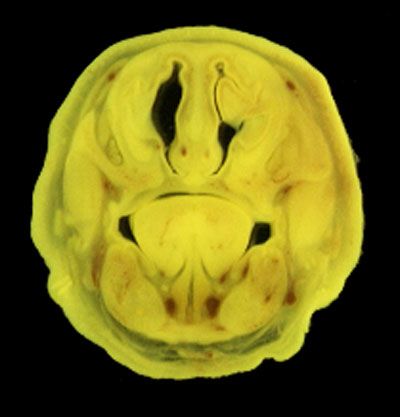

The images below show the normal appearance of Bouin's fluid fixed head sections in specimens at Day 21 of gestation (day mating observed = Day 0).

It is essential that both sides of each section is examined so that structures that exist is several sections can be visualised by the examiner in 3D.

Learning objective: Compare the diagrams with your own specimens and identify all of the structures that have been labelled.

Unlabelled Images